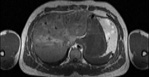

Visible Human male: Sectio transversalis 1507

CT

NMR

Pd                          / T2 \                         T1